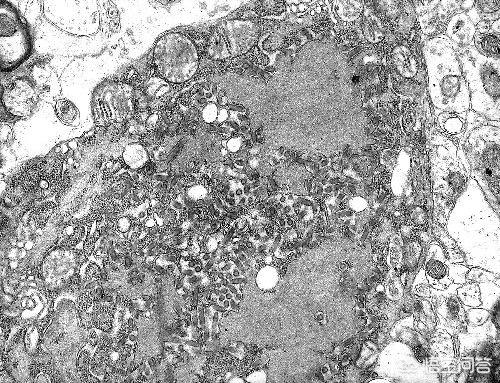

エボラ出血熱では、ウイルスは急速に拡散し、体内で大量に増殖し、さまざまな臓器を攻撃し、臓器を変性させ、壊死させ、徐々に分解させる。体内の臓器が壊死し、分解されるため、患者は壊死した組織を常に口から吐き出し、最終的には大量の内出血と脳障害によってほとんどが死亡する。

肛門の構造を口から吐き出す危険がある。意識があるうちに、内臓が徐々にドロドロになっていくのを感じるだろう。この病気には治療法がない。平均的な患者は発症から24時間以内に死亡する。